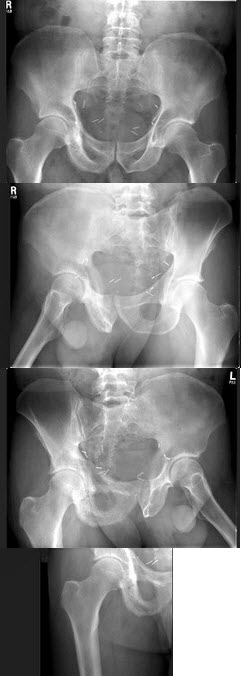

231、单项选择题

右髋关节疼痛,跛行1年多,无明显外伤史,双髋关节摄片如图,最可能的诊断是()

A.右髋关节退行性关节病

B.右髋关节创伤性关节病

C.右髋关节结核

D.右髋关节化脓性关节炎

E.右髋关节神经性关节炎

点击查看答案